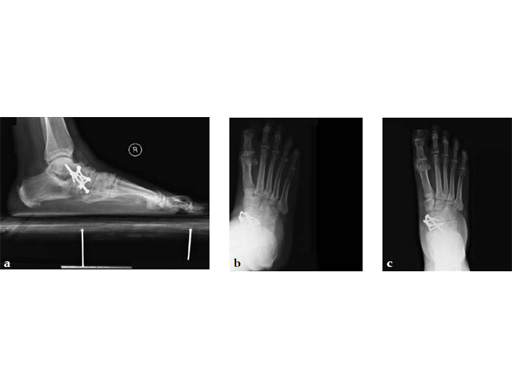

Case 1: First MP fusion VA-LCP

A 57-year-old woman has suffered rheumatoid arthritis for several years. She presented with pain and deformity in the left forefoot moreso than in the right. Clinical examination reveals severe hallux valgus deformity and dislocation of MP joints 11 through V, with synovitis.

Case provided by Juan Bernardo Gerstner, Cali, Columbia

A dorsal transtendinous approach was used and reaming of the first MT head and basal articular surface of the proximal phalanx was performed with the new reamers (see Fig. 3a-b).

A left MP fusion was performed as well as a II to V MT head resection arthroplasty, and fixed with K-wires for 4 weeks (see Fig. 4a-b). The patient was weight bearing immediately with wooden shoes and K-wires were removed 4 weeks postoperatively.